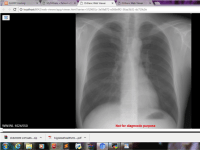

Using ORTHANC, an open source light weight DICOM server, and its REST API to query and retrieve patient’s data and radiology reports from a medical institution. The information retrieved will be cleansed and converted into DICOM image format. DICOM stands for Digital Imaging and Communications in Medicine. This file format is created to distribute and view medical images using a standardized file format.

a. Creation of radiology files in DICOM format, examination reports and patient’s medical records from hospital visits. DICOM stands for Digital Imaging and Communications in Medicine. This file format is created to distribute and view medical images using a standardized file format.

i) ORTHANC as an open source and light weight DICOM server for medical imaging, querying and retrieving patient’s data and radiology reports from a medical institution.

ii) An inbound web application for viewing medical examination reports and patient records. Complex applications can be built with ORTHANC Rest API